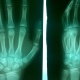

Добрый день, коллеги. Помогите, пожалуйста, разобраться с клиническим случаем. Пациент 2001 года обратился в мае к врачу после того, как ударил руку. Врач посмотрел пациента, решил не отправлять на...

Тип: Клиническое наблюдение

Область: Скелетно-мышечная система

Модальность: Rg

Дата: 29.09.2016 - 14:49